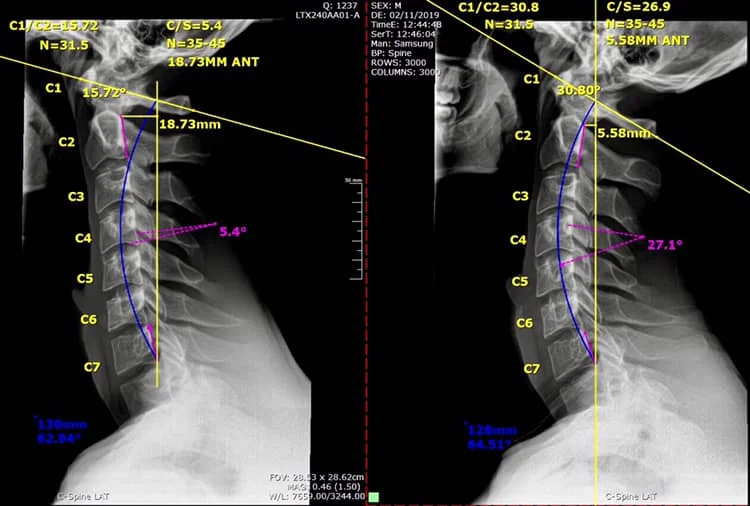

To remedy spine-related problems, assessments of X-ray images are essential to determine the spine and postural parameters. Chiropractic/manual therapy realignment of the structure of the spine can address a wide range of pain, muscle weakness, and functional impairments. Alternate methods to assess such spine problems are often indirect and do not reveal the root cause and could result in a significant misdiagnosis, leading to inappropriate treatment and harmful consequences for the patient. Radiography reveals the true condition and alignment of the spine; it eliminates guesswork. Contemporary approaches to spinal rehabilitation, guided by accurate imaging, have demonstrated superiority over primitive treatments. Unfortunately, there are well-meaning but misguided activists who advocate elimination or minimization of exposures in spine radiography. The radiation dose employed for a plain radiograph is very low, about 100 times below the threshold dose for harmful effects. Rather than increasing risk, such exposures would likely stimulate the patient’s own protection systems and result in beneficial health effects. Spine care guidelines need to be revised to reflect the potential benefits of modern treatments and the lack of health risks from low X-ray doses. This would encourage routine use of radiography in manual spine therapy, which differs from common pharmacologic pain relief practice.